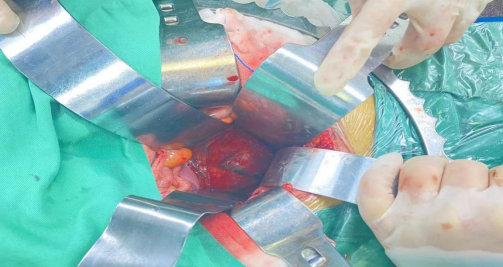

手术将肿瘤与肠管间置入纱扩垫,隔开肠管,保护肠管

手术将肿瘤与肠管间置入纱扩垫,隔开肠管,保护肠管,当天完成重离子灭活肿瘤